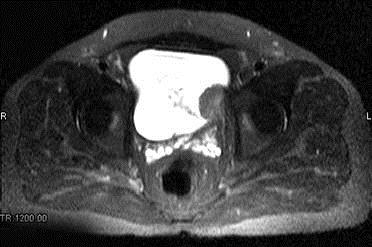

问题 男,59岁。血尿1个月。MRI检查如图所示。最可能的诊断是 ( )

选项 A、膀胱息肉 B、输尿管囊肿 C、膀胱癌 D、膀胱结石 E、膀胱内血块

答案 C